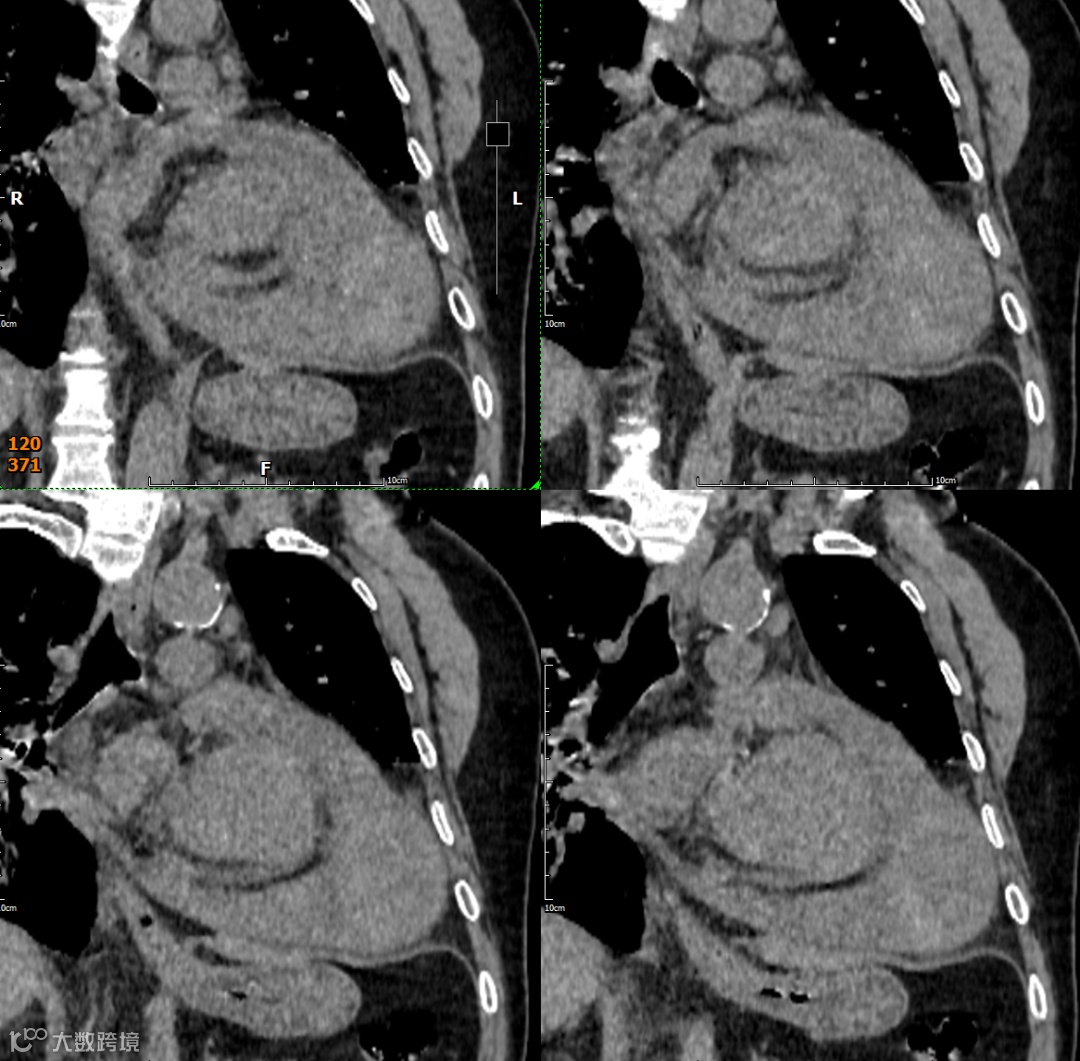

影像学检查

形态与位置:与左心室腔相邻的囊状、球状或葫芦状对比剂充盈腔。特征性的窄瘤颈是其关键。位置常在心包反折附近(下壁、后壁、侧壁)。

瘤壁:菲薄,无心肌密度!主要由心包(可能钙化)和血栓(不强化或延迟强化)构成。

瘤颈:清晰可见的、狭窄的开口(如瓶颈状)将假性瘤腔与左心室腔相连。破口处心室壁中断是直接征象。

腔内:可见对比剂充盈,内常有血栓(充盈缺损)。

心包:局部心包增厚、粘连、积液常见。瘤体常部分嵌入心包内。

多平面重建(MPR)与三维重建(3D): 对于清晰显示瘤颈的形态、大小、位置以及与左心室壁的关系至关重要。